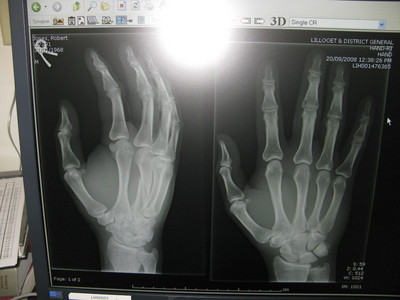

Just kidding, that’s Rob’s hand. If you look close you’ll see a nice spiral fracture of his driving finger. What a bummer.